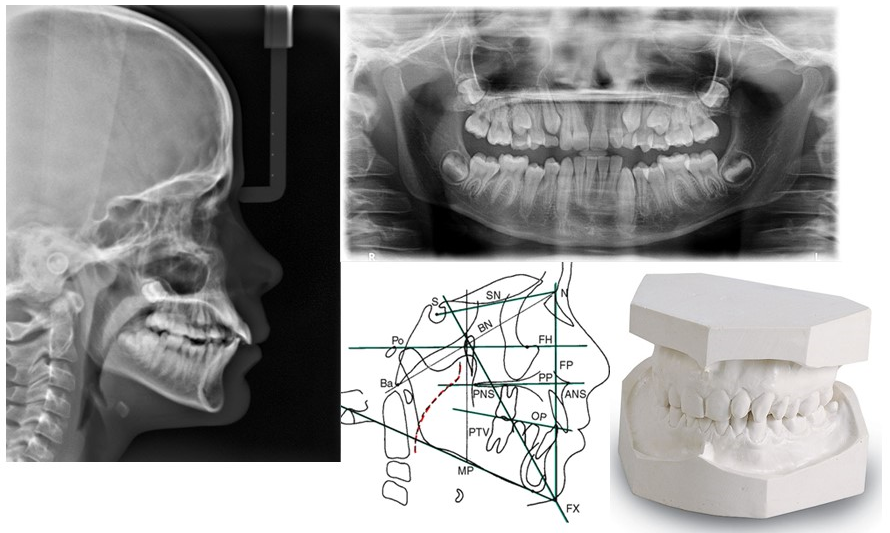

ESTUDIO DE ORTODONCIA

Siempre antes de colocar aparatología alguna a un paciente, lo primero será realizar el estudio pormenorizado de su caso. Se deben tomar los modelos del paciente, una serie fotográfica, una ortopantomografía, una teleradiografía y un trazado cefalométrico. En casos más complejos incluso se tomará un articulador, para evaluar el estado de la oclusión y de la articulación (ATM).

Todo esto nos proporciona la base para darte un buen diagnóstico y predecir dónde deberemos colocar tus dientes para dejar, no sólo una sonrisa bonita y armónica, sino una oclusión funcional que proporcione salud a tu ATM.

En S&CDental contamos con todos los medios para hacerlo en la propia clínica y como tenemos el más novedoso sistema de radiodiagnóstico digital, la radiación es mínima.